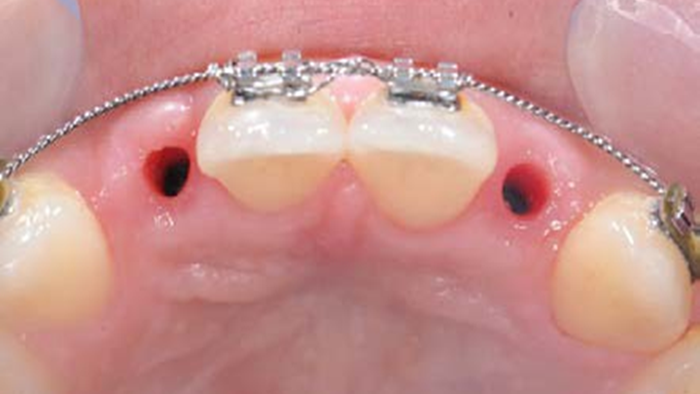

Clinical case: Patient-centered approach: treatment strategy for Root Membrane Technique & delayed implant placement

- Courtesy of Dr. Yoshiharu Hayashi, Japan -

“Advanced IntermezzoTM – one-piece solution for immediate placement & esthetic result in anterior region or narrow space.”